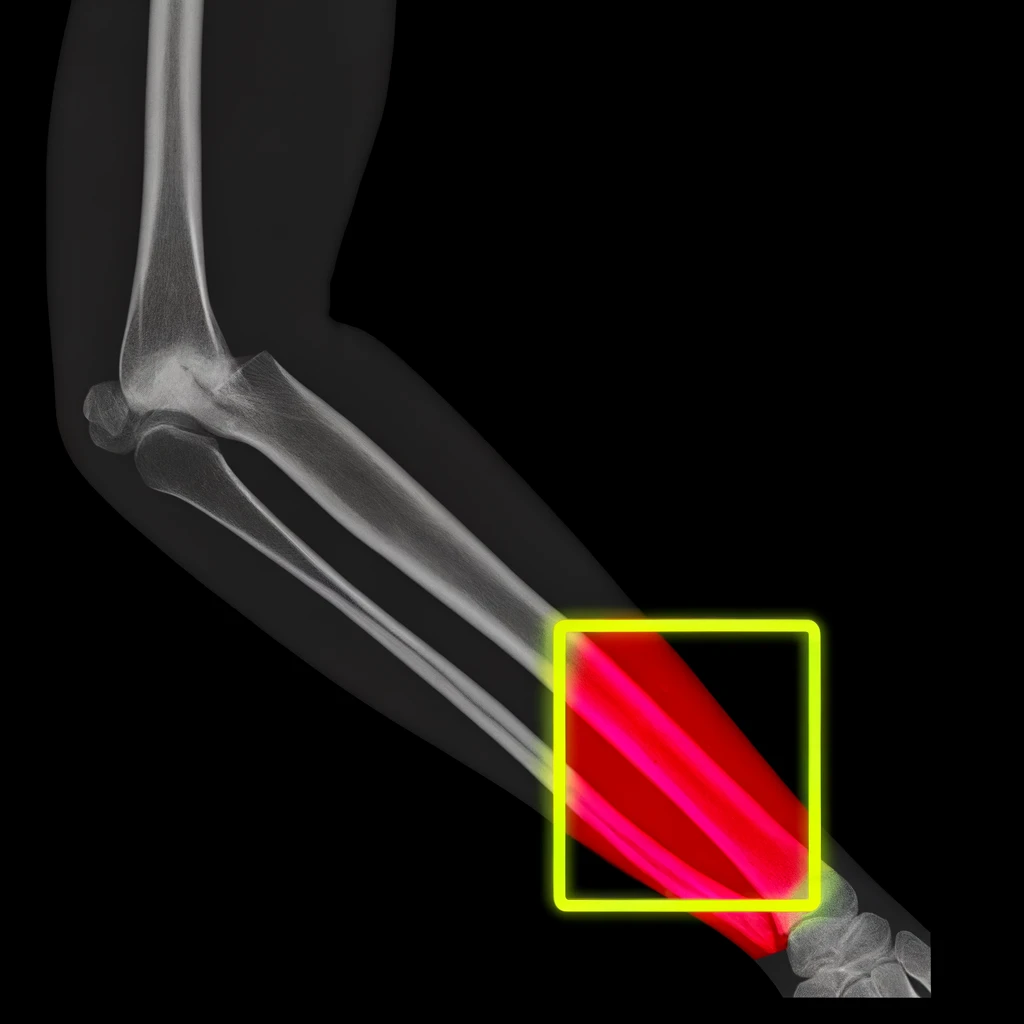

La medicina tradicional está experimentando una transformación gracias a la integración de soluciones tecnológicas avanzadas. XOR-Ray es pionero en este cambio, utilizando algoritmos de aprendizaje automático y procesamiento de imágenes para analizar radiografías. Este enfoque no solo mejora la precisión de los diagnósticos sino que también facilita recomendaciones de tratamiento personalizadas basadas en patrones identificados por la IA.